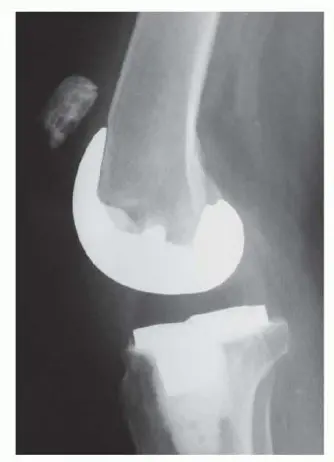

الأشعة السينية (Radiographs)

يجب الحصول على صور الأشعة السينية الأمامية الخلفية (AP) والجانبية للركبة. تُعد مقارنة هذه الصور مع الأفلام التي تم التقاطها مباشرة بعد الجراحة الأولية أو قبلها مفيدة للغاية.

- الرضفة العالية (Patella Alta): في حالات تمزق وتر الرضفة الكامل، غالبًا ما تكون الرضفة مرتفعة بشكل غير طبيعي (Patella Alta) بسبب فقدان الشد السفلي من الوتر الممزق. هذه علامة مميزة ومهمة.

- الرضفة المنخفضة (Patella Baja): في المقابل، قد تظهر الرضفة المنخفضة أو في وضع بعيد (distal position) في حالات تمزق وتر العضلة رباعية الرؤوس. ومع ذلك، فإن وضع الرضفة الطبيعي لا يستبعد تمزق وتر العضلة رباعية الرؤوس.

- الشظايا العظمية: قد تُظهر الأشعة السينية شظايا عظمية مرئية فوق أو أسفل الرضفة أو بالقرب من الحدبة الظنبوبية، مما يشير إلى انفصال الوتر عن العظم (avulsion).